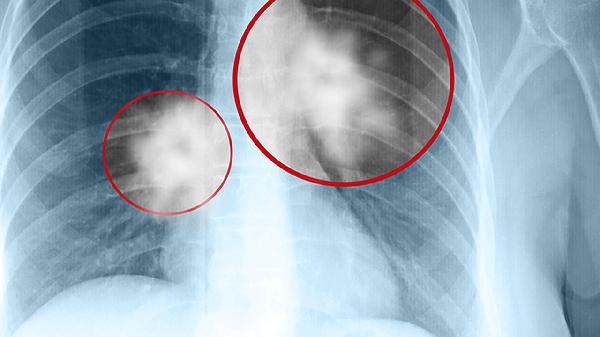

肺结节恶性肿瘤不会传染。肺结节恶性肿瘤是由细胞异常增生形成的,其发生与遗传、环境、吸烟等因素有关,但并非由病原体引起,因此不具备传染性。肺结节恶性肿瘤的治疗需要根据具体情况采取个体化方案,通常包括手术、放疗、化疗等综合治疗手段。